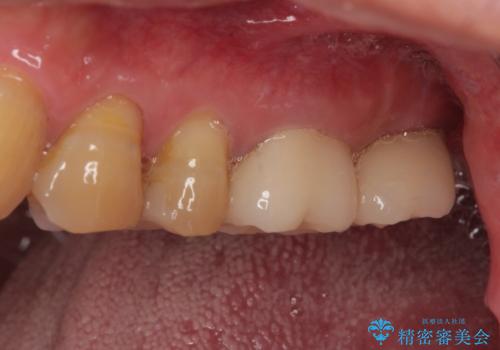

欠損した奥歯 インプラントによる補綴治療

奥歯の欠損部はインプラントによる補綴治療を、手前の破損したクラウンは作り替えをご希望でした。

口があまり開かず、インプラントの埋入角度がやや斜めとなりましたが、機能的には全く問題なく治療を終えることができました。